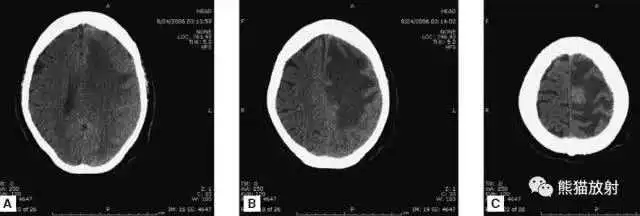

缺血性脑卒中

- 早期:脑水肿,灰白质分界模糊,脑沟消失;

- 中期:病变区域密度减低;

- 晚期:脑实质体积缩小。

A:陈旧性脑梗死,右枕叶体积缩小;

B:左枕叶急性脑梗死,灰白质分界模糊,脑沟消失;

另一患者:

C、D:亚急性期脑梗死,低密度,无明显占位效应。

▲

左侧大脑中动脉供血区脑梗死(亚急性期):

低密度,轻度水肿

缺血性脑卒中发作2-4天时,占位效应最明显。